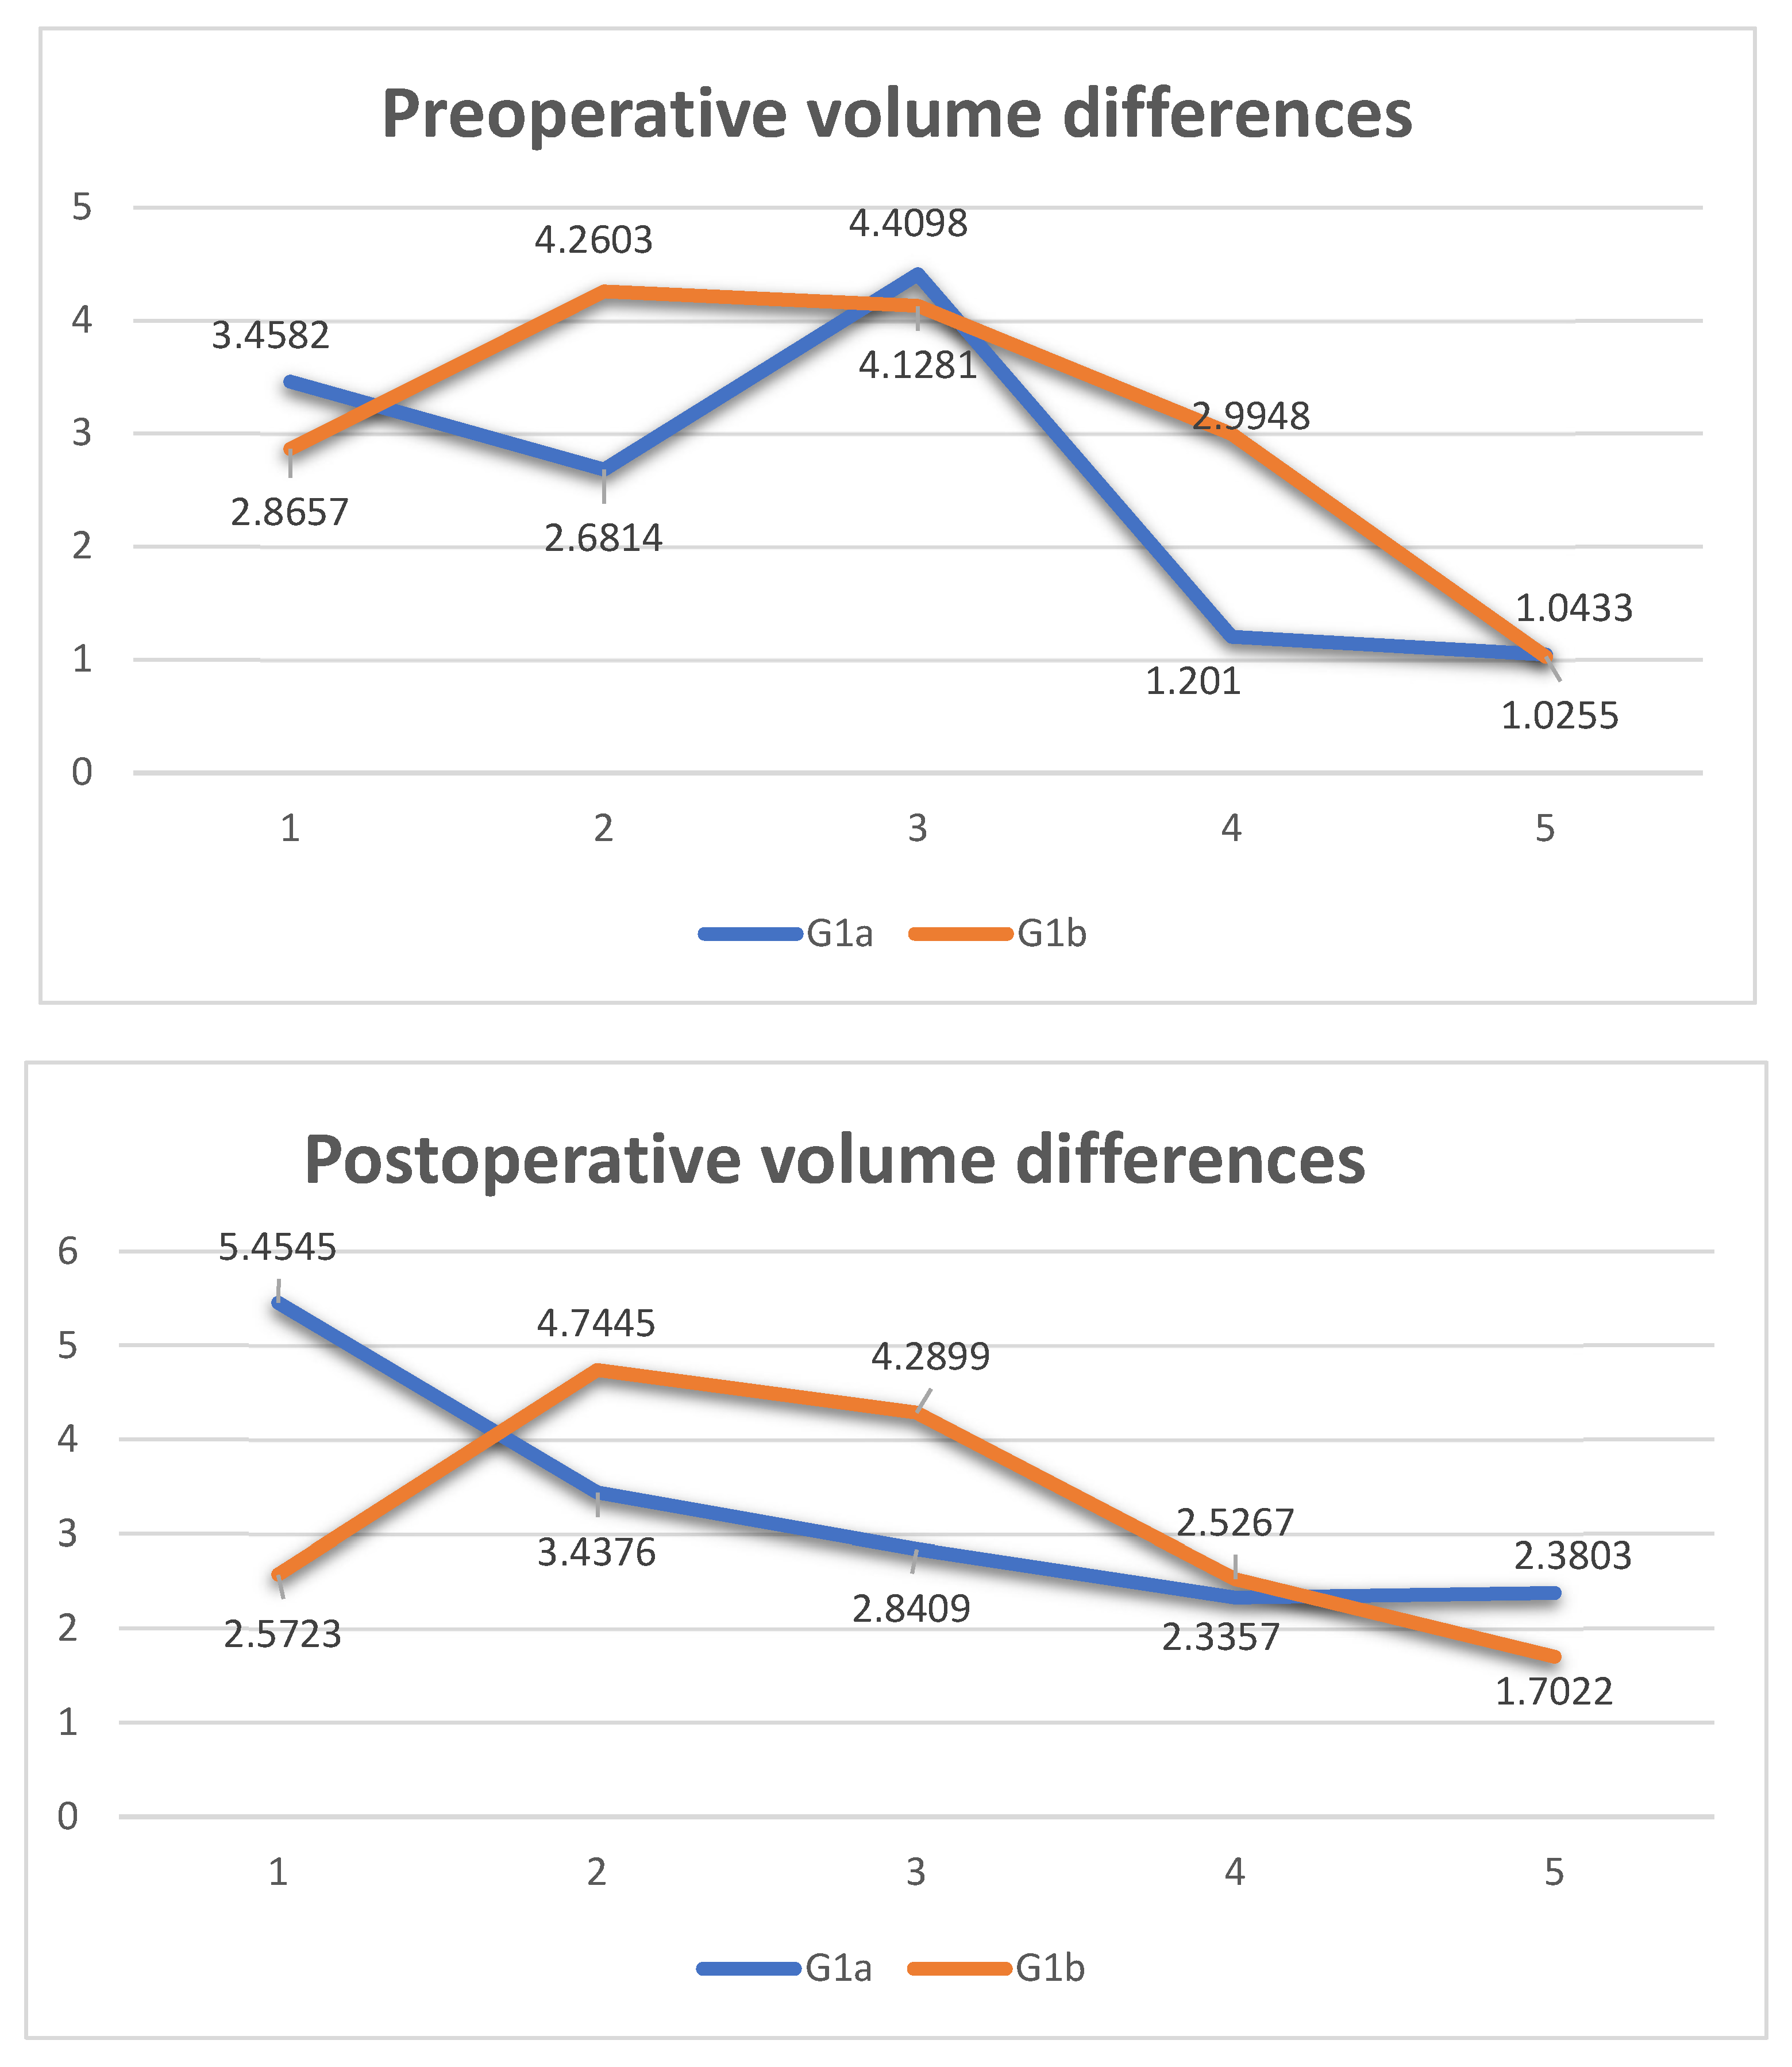

- Measurement of orbital volume using Osirix software (Version 12.0) (Pixmeo SARL, CH-1233 Bernex, Switzerland) on the new CT examination. This was carried out both semi-automatically and manually. For each patient, the orbital volume on the preoperative CT was calculated for both healthy and fractured orbits. On the postoperative CT, however, the orbital volume reconstructed with titanium mesh was calculated. We then calculated the difference in volumes between healthy and traumatized orbit, both before and after surgery. Finally, we evaluated the recovery difference, which is made up of the difference between the two volumes, pre-op and post-op, of the traumatized orbit.

3. Results

| Age | Sex | Type of Incidente | Fracture Side | Volume cm3 Right Orbit | Volume cm3 Left Orbit | Volume cm3 Mesh Orbit | Vol- cm3 Difference Pre-op | Vol- cm3 Difference Post-op | Vol- cm3 Recovery Difference | Surgery Time in Min | |

|---|---|---|---|---|---|---|---|---|---|---|---|

| 1 | 33 | Male | aggression | Right | 29.0359 | 25.5777 | 23.5814 | 3.4582 | 5.4545 | −1.9963 | 95 |

| 2 | 59 | Male | aggression | Right | 23.9741 | 21.2927 | 20.5365 | 2.6814 | 3.4376 | −0.7562 | 80 |

| 3 | 37 | Male | car accident | Left | 23.204 | 27.6138 | 24.7729 | 4.4098 | 2.8409 | 1.5689 | 75 |

| 4 | 74 | Male | accidental fall | Left | 25.2797 | 26.4807 | 24.145 | 1.201 | 2.3357 | −1.1347 | 85 |

| 5 | 41 | Male | aggression | Left | 25.9815 | 27.0248 | 24.6445 | 1.0433 | 2.3803 | −1.337 | 60 |

| Age | Sex | Type of Incidente | Fracture Side | Volume cm3 Right Orbit | Volume cm3 Left Orbit | Volume cm3 Mesh Orbit | Vol- cm3 Difference Pre-op | Vol- cm3 Difference Post-op | Vol- cm3 Recovery Difference | Surgery Time in Min | |

|---|---|---|---|---|---|---|---|---|---|---|---|

| 1 | 19 | Male | sports trauma | Right | 27.6954 | 24.8297 | 25.1231 | 2.8657 | 2.5723 | 0.2934 | 40 |

| 2 | 72 | Male | car accident | Left | 24.0521 | 28.3124 | 23.5679 | 4.2603 | 4.7445 | −0.4842 | 35 |

| 3 | 37 | Male | aggression | Right | 21.9546 | 26.0827 | 21.7928 | 4.1281 | 4.2899 | −0.1618 | 40 |

| 4 | 30 | Male | sports trauma | Left | 21.7904 | 24.7852 | 22.2585 | 2.9948 | 2.5267 | 0.4681 | 45 |

| 5 | 19 | Male | sports trauma | Left | 31.149 | 32.1745 | 30.4723 | 1.0255 | 1.7022 | −0.6767 | 35 |